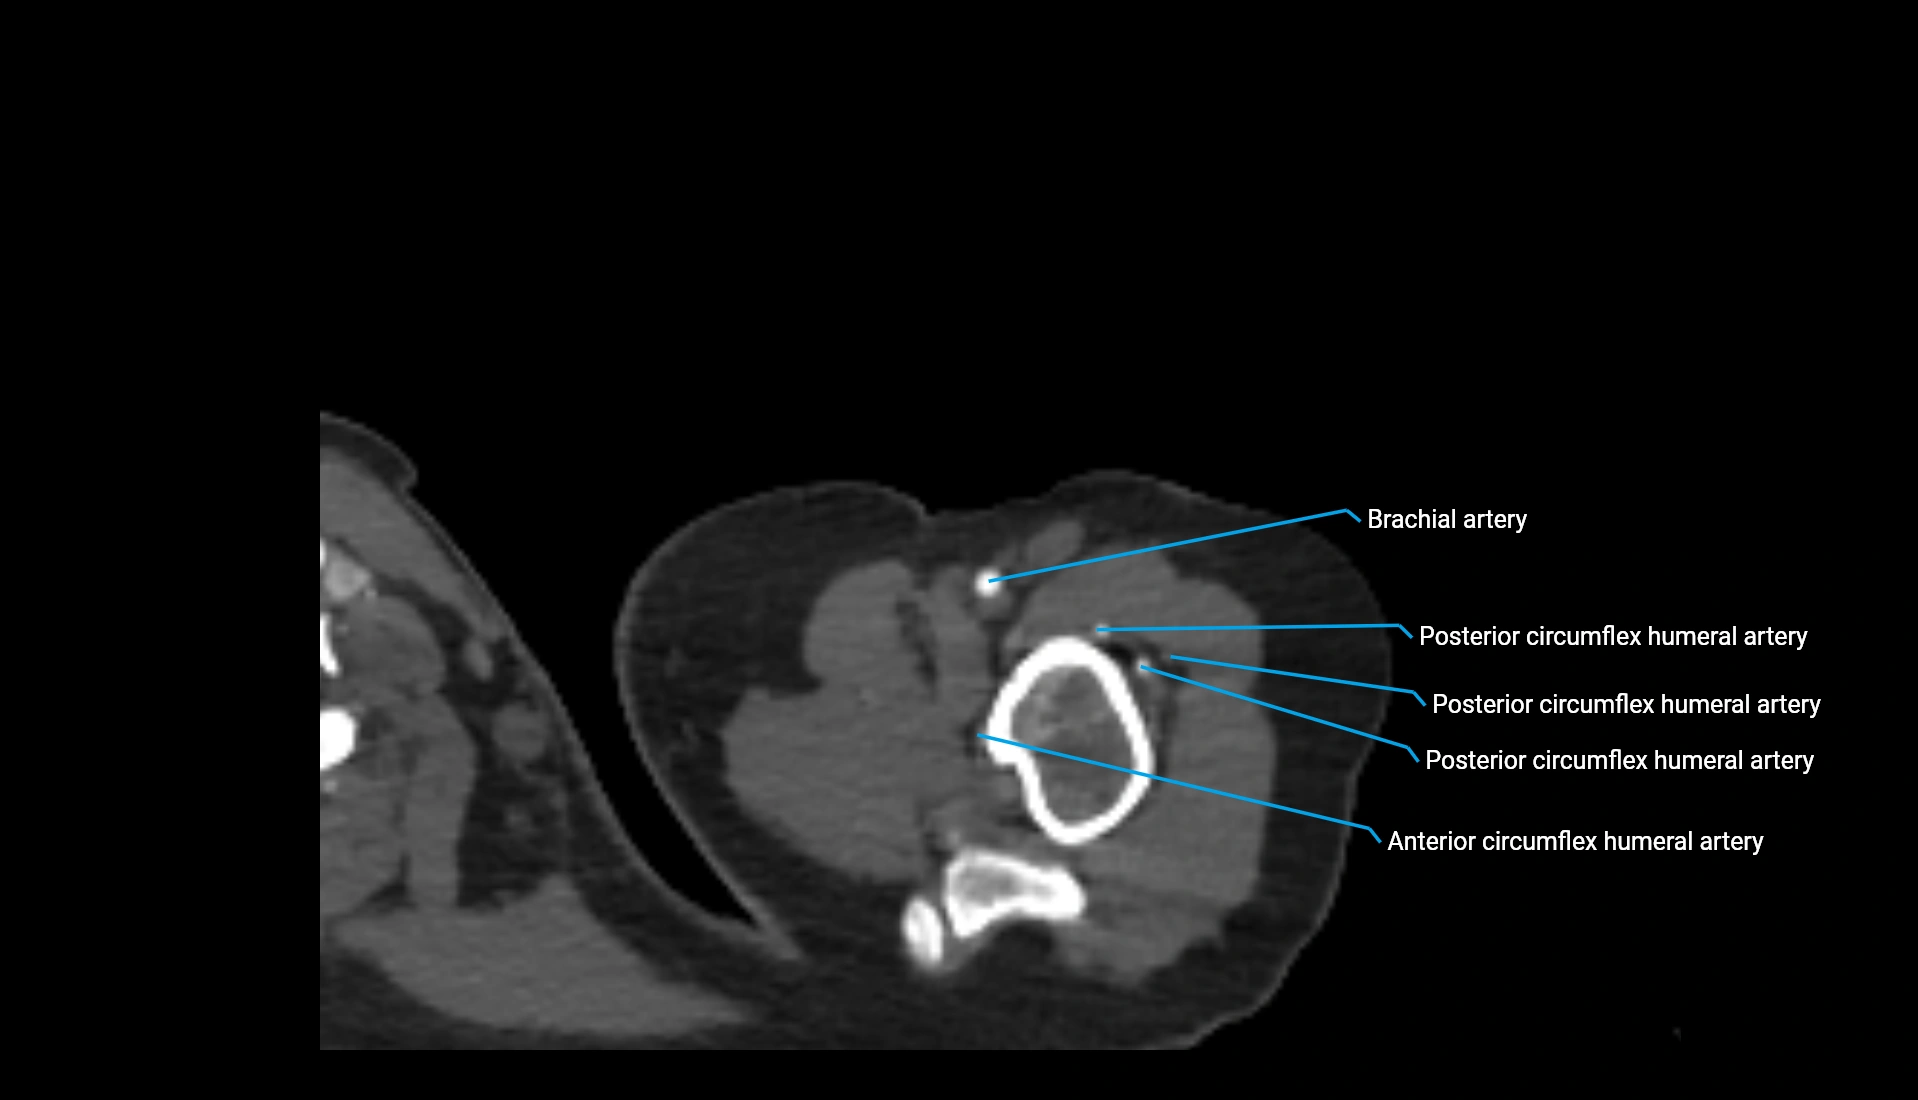

CT Appearance

Non-Contrast CT:

• Cortex: High-density, sharply defined

• Subchondral bone: Dense cancellous matrix

• Articular surface: Smooth concave contour articulating with the capitellum

• Excellent for evaluating bone integrity, alignment, and subtle fractures

Post-Contrast CT:

• Bone: No enhancement

• Joint capsule and synovium: Mild enhancement outlining the joint

• Improves contrast between soft tissues and bony margins

• Useful in detecting subtle joint abnormalities or postoperative changes